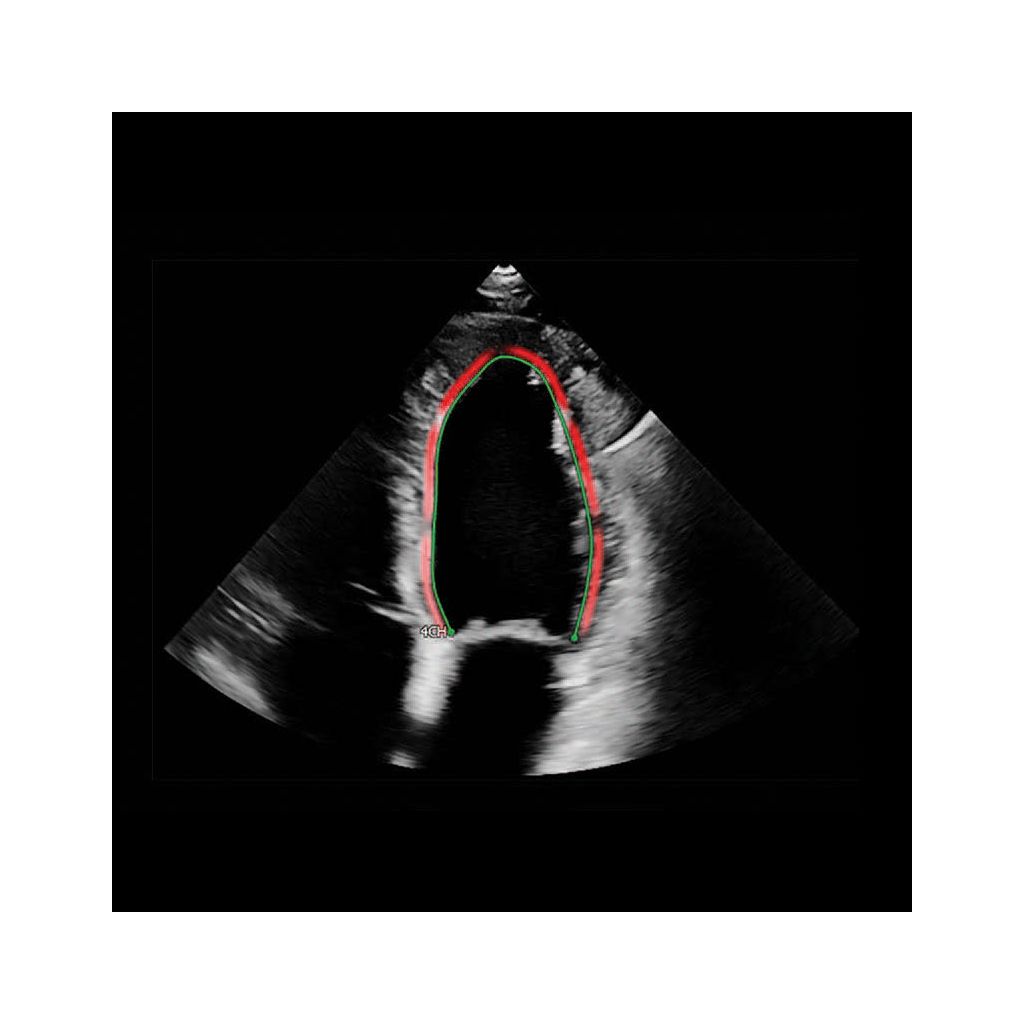

Clinical Image - AutoStrain LV– Affiniti CVX

Auto Contour Placement

A specialized contour detection module for the respective apical view is applied to each of the three image sequences and operates in three steps. First, a complete R-R cycle – end-diastole (ED) start to ED end – is selected from each sequence. Second, in the ED start frame of that cycle, the left ventricle (LV) is automatically located. Third, a view-specific deformable endocardial contour model is aligned to the individual image content (Figure 2). The same approach is applied for RV Auto Contour Placement while the initial LA contour is placed in the end-systolic (ES) frame (Figure 2).

Longitudinal strain is measured at the endocardial border as indicated by the green line. Instantaneous endocardial strain is visualized by color-coding close to the endocardial border.